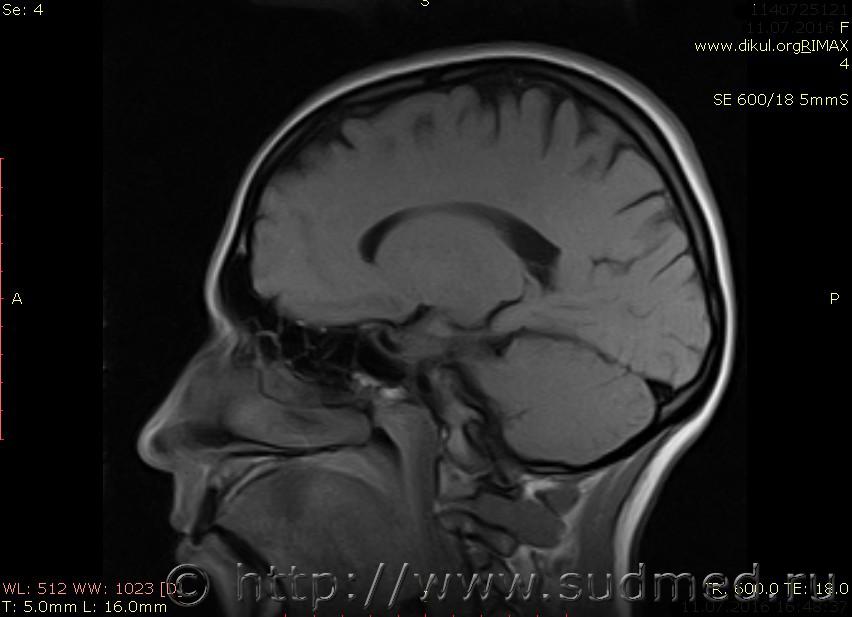

МРТ головного мозга показало: МР-данных за наличие очаговых изменений в веществе головного мозга на момент исследования не выявлено. МР-признаки нарушения соотношения в атланто-осевом суставе. Определяется ассиметрия положения зубовидного отростка С2 относительно боковых масс С1(справа 6,5; слева 4 мм.)

Сама по себе эта информация даёт основания подозревать вывих первого шейного позвонка, но однозначно не свидетельствует о наличии вывиха. Нужно смотреть на снимках наличие реакции со стороны мягких тканей, в т.ч. связочного аппарата, нужно анализировать особенности неврологической патологии, её динамику и проч.

Запрошен электронный вариант снимков из учреждения, где делалось МРТ. Т.к. с самого снимка делать копии не получается,очень мелкие кадры. Завтра попробую вставить в сообщение. (Но СМЭ снимок не смотрел, смотрел только мед.карту, в которой находилось описание МРТ).

Посмотрите пожалуйста снимки, надеюсь на них видны позвонки С1,С2?

Прошу прощения, попробую снова прикрепить файлы. Данные учреждения и пациента убраны.